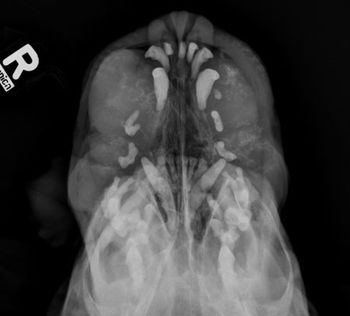

Examine the imaging results to help solve this pug's problem.

Look at the radiographs and determine the most likely diagnosis.